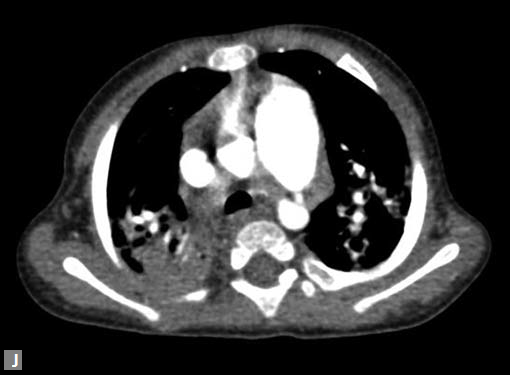

Filling defects (Figs 16A and B) may be seen in main

pulmonary artery (MPA), left pulmonary artery (LPA) and

right pulmonary artery (RPA), interlobar artery, segmental

divisions (Figs 17A and B). On occasions, detection in distal

On occasions, thromboembolism can also be seen in right

ventricle and less commonly in pulmonary veins. Systemic

vein thrombus (innominate veins, SVC, IVC) sometimes

accompanies pulmonary thromboembolism (Figs 18A and B).